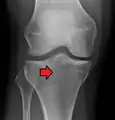

• Type II = Lateral tibial plateau fracture with depression,

This is a combined cleavage and compression fracture and involves vertical split of the lateral condyle combined with depression of the adjacent load bearing part of the condyle. Caused by a valgus force on the knee; it is a low energy injury, typically seen in individuals of the 4th decade or older with osteoporotic changes in bone. Most common, and make up 75% of all tibial plateau fractures. There is a 20% risk of distraction injuries to the medial collateral ligament. May include distraction injury to the medial collateral ligament or anterior cruciate ligament.

Lateral Tibial Plateau fracture XRay with Depression